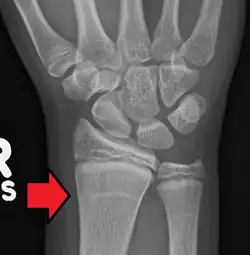

| Growth arrest lines in a child with an underlying bone disease | |

Growth arrest lines, also known as Harris lines, are lines of increased bone density that represent the position of the growth plate at the time of insult to the organism and formed on long bones due to growth arrest. They are only visible by radiograph or in cross-section. The age at which the lines were formed can be estimated from a radiograph. Harris lines are often discussed as a result of juvenile malnutrition, disease or trauma. Other studies suggest a reconsideration of Harris lines as more of a result of normal growth and growth spurts, rather than a pure outcome of nutritional or pathologic stress.[1] The lines are named after Henry Albert Harris (1886–1968), professor of anatomy at the University of Cambridge.[2]